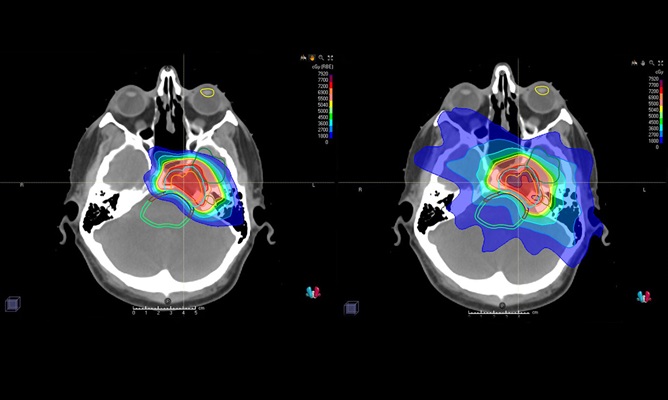

Photon beams enter the brain and go through the tumor and beyond, delivering radiation throughout their travel path. Protons are different in the way they deliver the most radiation at the end of their path, so tissues beyond the tumor don’t get affected.

Patient brain scans show how proton therapy (left) targets brain tumors with minimal radiation going to surrounding tissue and structures, whereas traditional photon radiation (right) can damage surrounding brain tissues and structures.